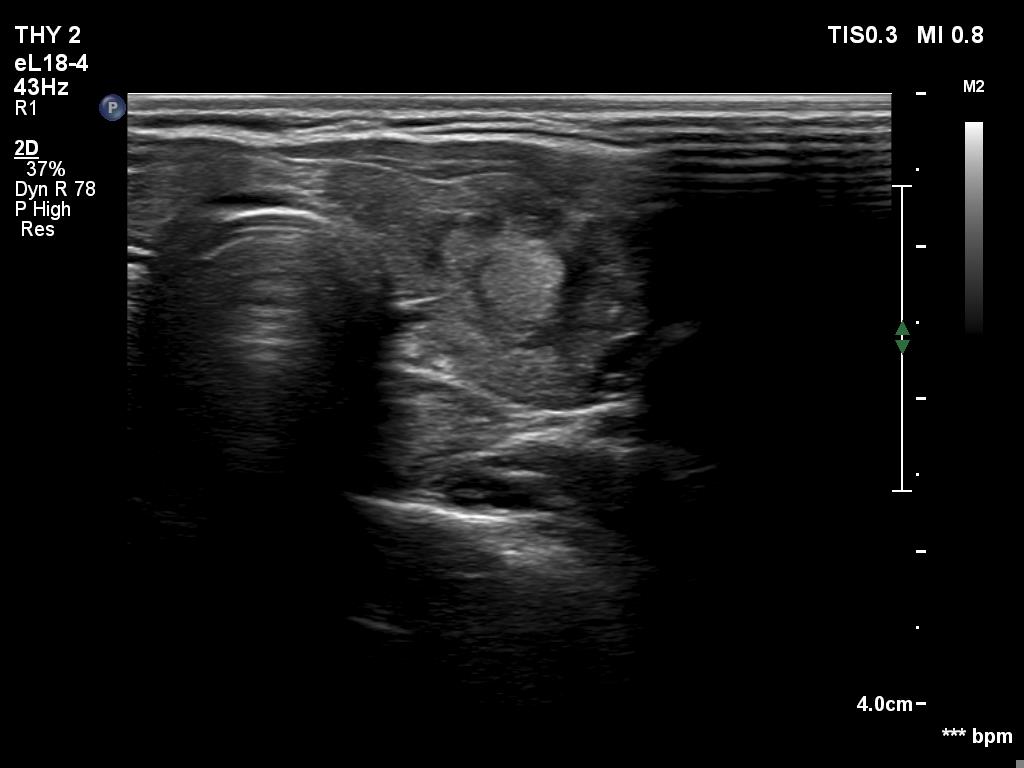

Right lobe, longitudinal scan

This is the usual course of Graves' disease regarding the change in echo pattern - before, during and after the activity of the autoimmune process. The only exception is the change in the size of the thyroid. In most cases, the thyroid increases during the activity of the disease, then returns to normal. However, in this patient the age counts: at the first examination, the patient was only 15-year-old.